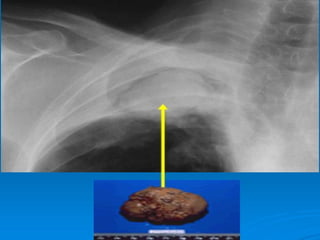

Opacité systématisée au LSD rétractile

DDB pleines en doigt de gant   Après Ttt corticoïde

 RX thorax ( face + profil) :

   IMAGES PERMANANTES :

- bronchectasies proximales : opacités kystiques ou

en rails, volontiers volumineuses.

Dilatation des bronches kystique bilatérale